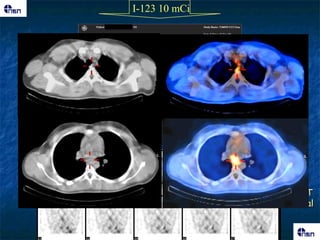

I-123 10 mCi

I-123 10 mCi SPECT coronal